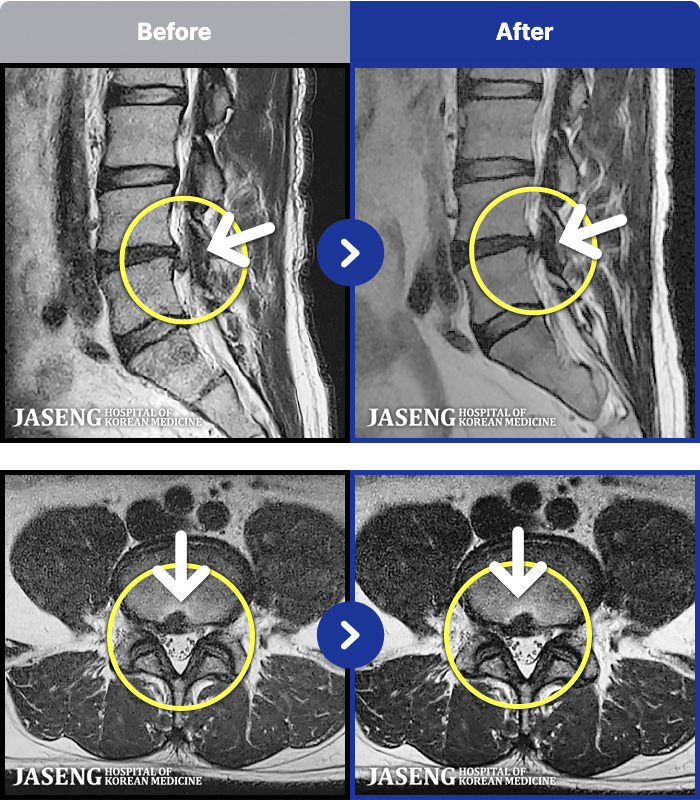

1,291 MRI ũ ʸ Ȯϼ.

[] 03.04.01~09.11.01